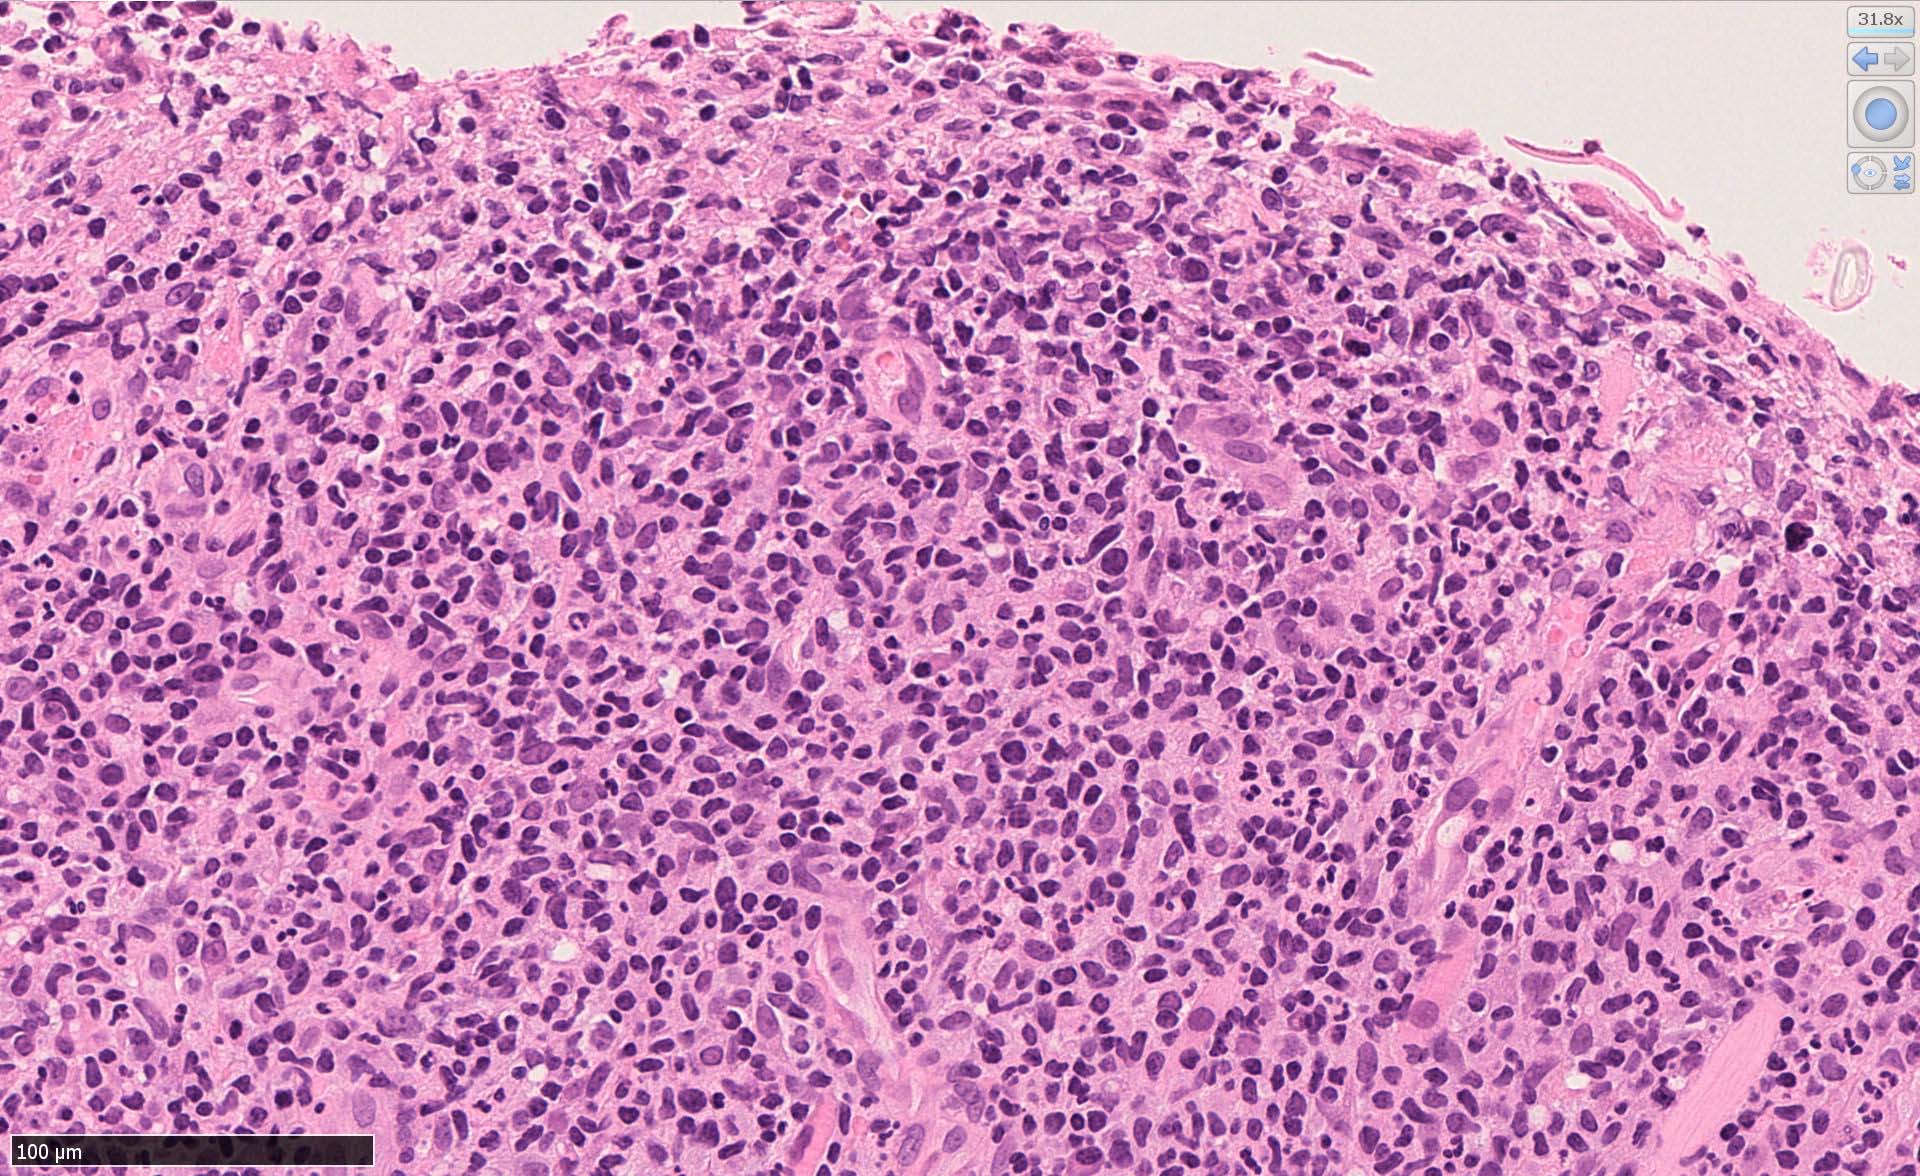

EBV陽性粘膜皮膚潰瘍(EBVMCU)は、EBV陽性の異型大型B細胞および/またはHodgkin/ Reed-Sternberg (HRS)様細胞を含む多形リンパ球浸潤を伴うリンパ増殖性疾患(pleomorphic pattern)で、

典型的には免疫不全/調節障害を有する患者の粘膜および皮膚に発現する。--WHO 5th classificationに記述された定義